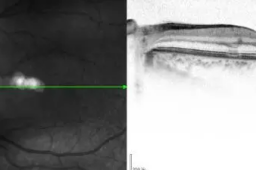

【20:05:00】 近日,浙江温州市中西医结合医院接诊的一名患者,被诊断为急性黄斑区神经视网膜病变。据悉,患者在感染新冠后突然视力下降,看不清东西。

【21:05:00】 近日,浙江温州市中西医结合医院接诊的一名患者,被诊断为急性黄斑区神经视网膜病变。据悉,患者在感染新冠后突然视力下降,看不清东西。

【22:05:00】 近日,浙江温州市中西医结合医院接诊的一名患者,被诊断为急性黄斑区神经视网膜病变。据悉,患者在感染新冠后突然视力下降,看不清东西。